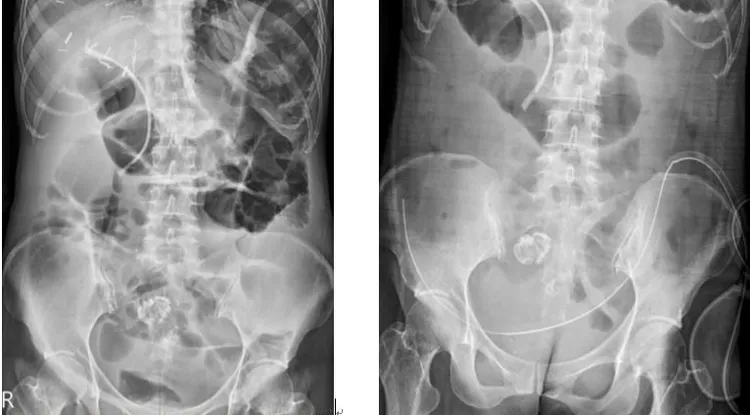

林女士接受腹腔高壓氣霧化療合併免疫細胞療法,成功將原本嚴重腸阻塞(左圖)癌細胞消失(右圖)。中國附醫提供